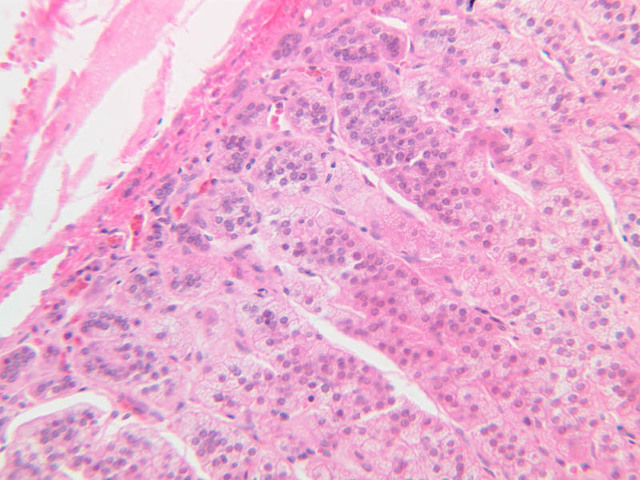

Examine slide B-56 (H&E [2.5x, 10x, 20x, 40x-labeled] [10x, 20x, 40x-labeled] [20x, 40x] [10x, 20x, 40x-labeled] [10x, 20x, 40x]). The connective tissue capsule of each parathyroid gland is continuous with that of the thyroid gland. It extends into the substance of the gland, dividing it into poorly defined lobules. Fat cells may separate the groups of cells and increase with age. Note the rich capillary network. The parenchyma is composed of two types of cells: (1) Principal or chief cells and (2) oxyphil cells. The polygonal chief cell is by far the more numerous cell type. Its nucleus is centrally located and has a vesicular chromatin pattern with a prominent nucleolus and its cytoplasm stains rather lightly. Oxyphil cells, which are less regular in shape and considerably larger than chief cells, are scattered singly or in small clusters. Their nuclei are smaller and more condensed than those of the chief cells and, owing to a very rich complement of mitochondria, their cytoplasm is distinctly acidophilic.